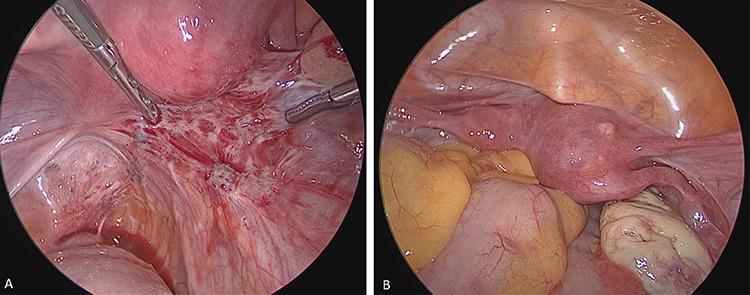

Endometriosis is one of the most common benign diseases in women of reproductive age. Nearly all gynecological offices and clinics will contain patients with endometriosis; the frequency and severity of the disease will vary from one setting to another. Adjoining specialties, such as internal medicine, general medicine, surgery, urology, orthopedics, neurology and psychosomatic medicine, will be challenged directly or indirectly by various forms of endometriosis and its sequelae. The disease is characterized by pelvic pain, dysmenorrhea, dyspareunia and sterility. Even now, several years may elapse between the onset of the disease and its diagnosis. The diagnosis of endometriosis is complicated by the diversity of the symptoms. A precise documentation of the patient’s medical history and thorough diagnostic procedures are essential to establish a robust diagnosis. This article will discuss the perioperative considerations, diagnosis and treatment of endometriosis.